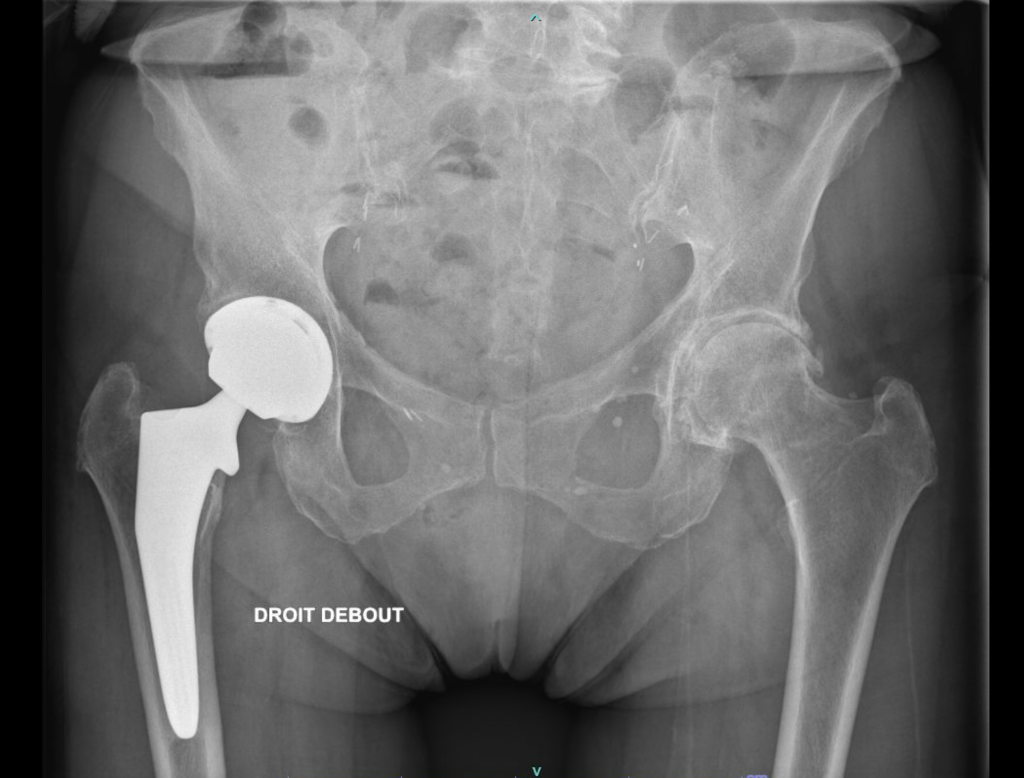

Il s’agit du remplacement de l’articulation par un couple de frottement synthétique. Comme pour l’articulation native, une tête sphérique synthétique s’articule dans une hémisphère creuse. Les matériaux habituellement utilisés sont la céramique (couple céramique/céramique), l’inox et le polyéthylène (couple métal/PE).

Ce pivot est maintenu dans l’os par 2 implants prothétiques: la tige fémorale et le cotyle prothétique. Chaque implant est habituellement revêtue d’hydroxyapatite (un des composant de l’os) permettant son intégration après impaction. Il existe également des implants à cimenter, polis, qui sont utilisés en cas de qualité osseuse insuffisante.

Les matériaux usuels qui entrent dans la composition du cotyle prothétique sont le Chrome-Cobalt et le Titane pour la tige fémorale.